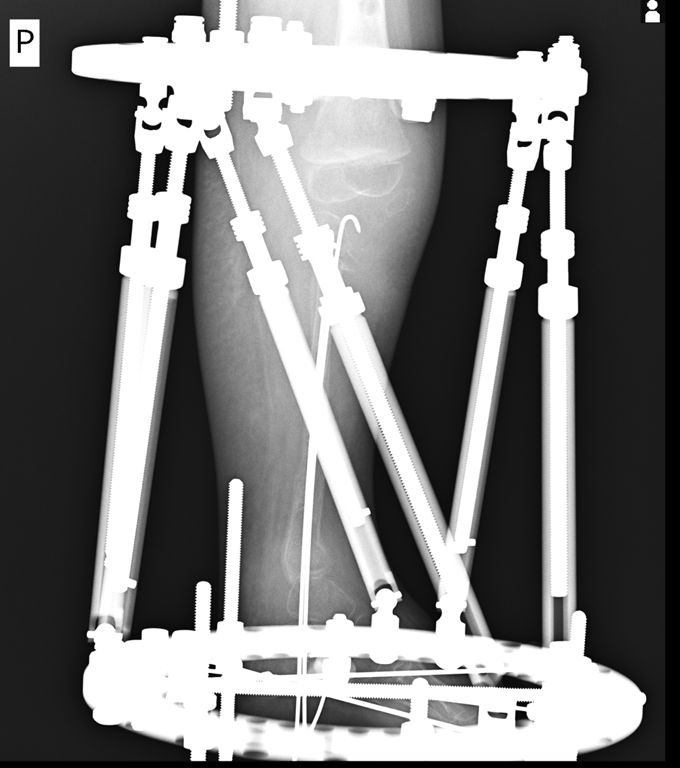

Dziewczynka urodziła się ze zniekształconą kością piszczelową. Jej noga była krótsza i wygięta pod nienaturalnym kątem. Lekarze ze Szpitala imienia Wiktora Degi przeprowadzili nowatorską operację. Najpierw zrekonstruowali stawy: kolanowy i skokowy, a później zaczęli wydłużać kość. Dzieci z taką wadą rodzą się jedno na milion - mówi dr Milud Shadi.

Taka wada jest bardzo ciężka. Dziecko nie ma jeszcze czterech lat i już ma skróconą nóżkę o 12 cm. Do tego nieprawidłowe kolano, nieprawidłową stopę. Dziecko jeszcze ma aparat zewnętrzny na nodze, który planujemy za miesiąc usunąć. Ona chodzi w aparacie i ma wyrównywaną nogę. Jakbyśmy nic nie robili, to w wieku dojrzałości - dla dziewczynki 14 lat - to to skrócenie nogi by było 25 cm.